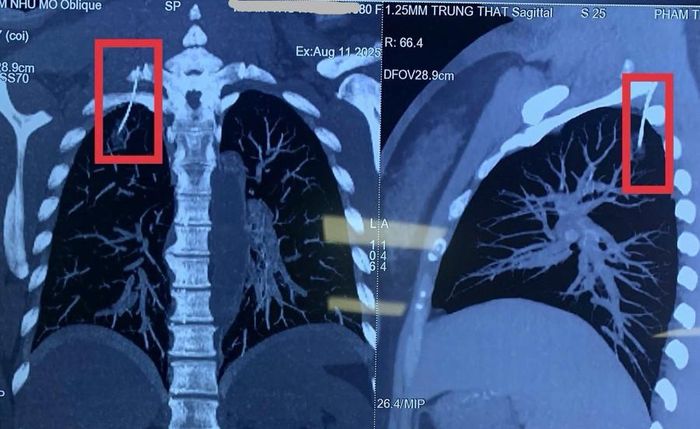

H́nh ảnh chụp cắt lớp vi tính dựng h́nh phát hiện dị vật chọc vào màng phổi phải bệnh nhân. Ảnh: Khoa Ngoại Tổng Hợp 2 - Bệnh viện Thanh Nhàn.

Lo lắng, gia đ́nh đưa bà H. đến bệnh viện để kiểm tra. H́nh ảnh chụp cắt lớp vi tính dựng h́nh phát hiện một dị vật kim loại đă xuyên qua vùng vai, chọc vào khoang màng phổi phải, vị trí ở đỉnh phổi. Các bác sĩ xác định đây chính là kim châm cứu bị găy hoặc đi lạc trong quá tŕnh thực hiện.